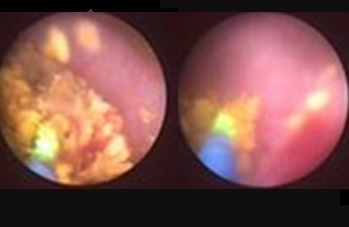

膀胱肿瘤